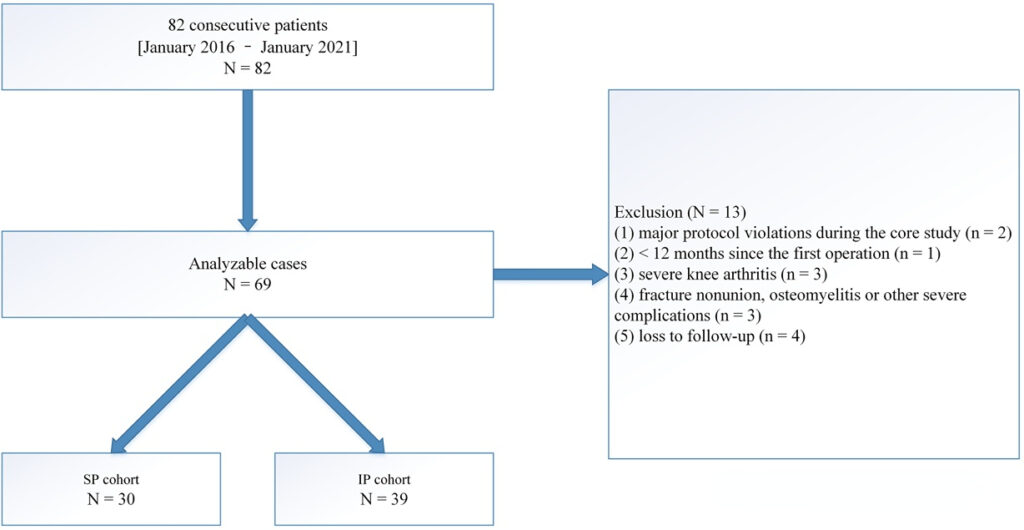

In this study, the authors included 69 patients, of whom 30 were removed suprapatellar and 39 were removed infrapatellar. The suprapatellar group had a higher Lysholm score and a lower VAS score.